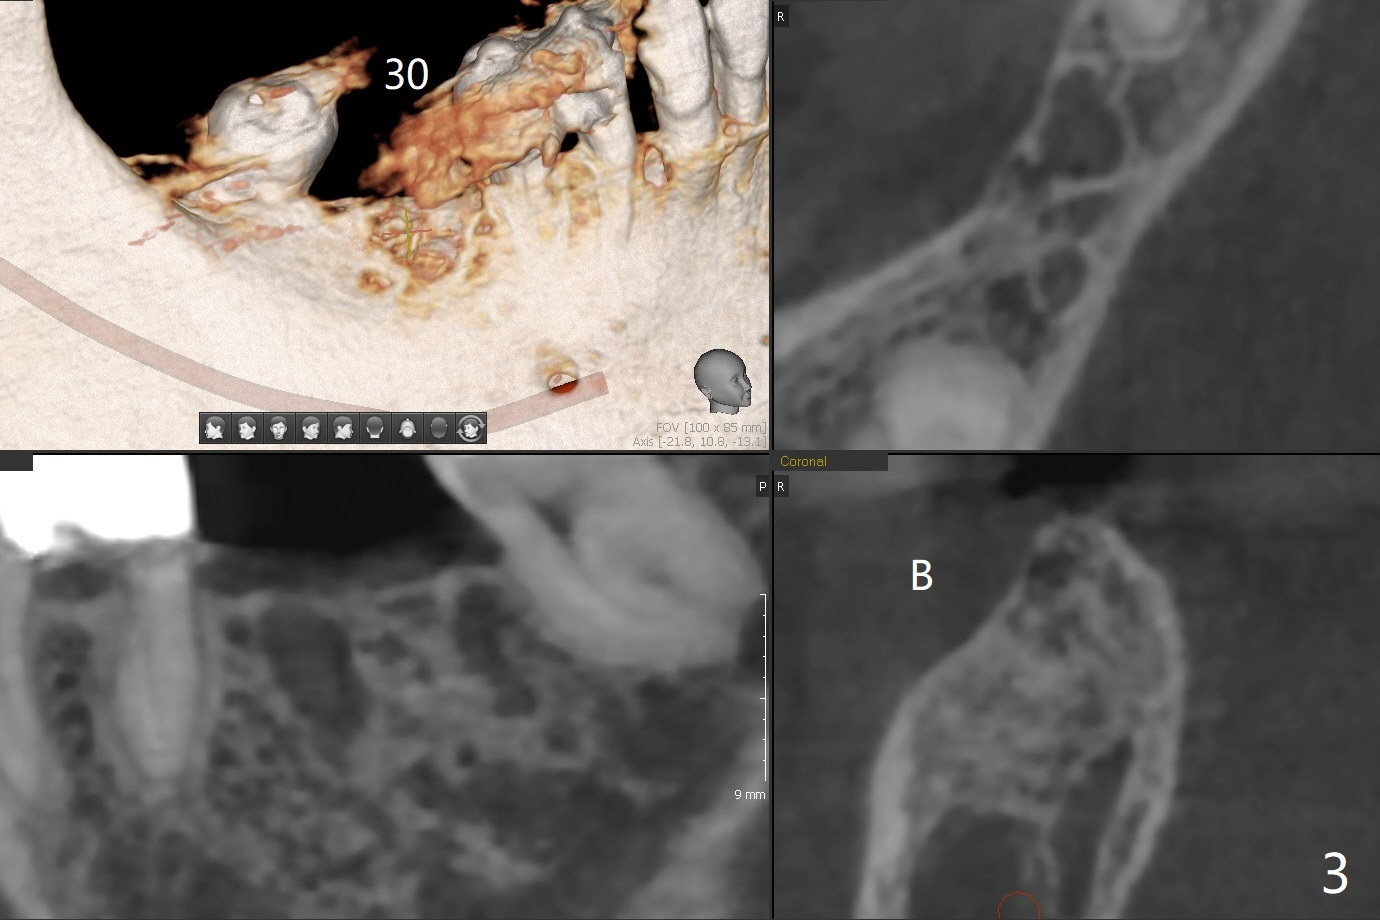

A 64-year-old woman with partial edentulism requests an implant for #30 after #29 crown temp bond cementation (Fig.1). The buccal, crestal and lingual cortex is equally thin (no deviation). The medulla is porous. The average bone density is 600 units. Ask the patient about osteoporosis treatment. A 4.5x10 mm implant with deep placement is going to have 2 mm bone buccal and lingual. Underprep is necessary (the last drill 3.5x10 mm). Due to metal scattering from amalgam from #28,29,31, a larger field view of CT is taken (Fig.2). Although the cancellous bone looks porous (Fig.3), the average bone density is 1000 units. The 2nd analysis shows that the ridge is narrower, allowing safe placement of a 4 mm implant (Fig.4,5). In spite of keratinized gingiva in the edentulous area, incision will be made to make sure the ridge top is being flattened by bone trimmer. If it is insufficient, use rotary instruments.